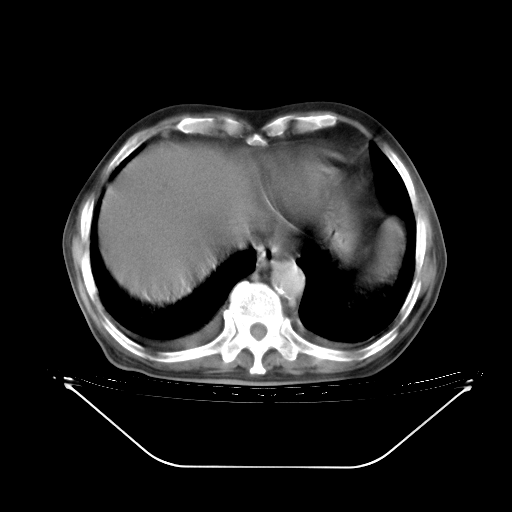

今天复查肺部CT,发现双肺广泛磨玻璃样改变。所以我把3月19日和5月9日相隔50天的肺部CT上传。请大家会诊。

5月9日肺部CT(在4月27日齐鲁医院肺部CT描述部分肺组织磨玻璃样改变,12天后肺组织广泛磨玻璃样改变)

大致读了系列胸部CT:纵隔窗无明显异常,肺窗:从4、27至今:主要是双肺中下野外带可见毛玻璃样改变,目前处于急性肺泡炎阶段,至于原因考虑1、结替组织或胶原血管性疾病所致?2、恶性疾病如恶组在肺部所致的表现或细支气管肺泡癌?3、药物或其它原因如肺蛋白沉着症所致肺泡炎目前不太可能?总之,明天就去请我院的呼吸科、感染科、血液科和临免专家会诊哈。